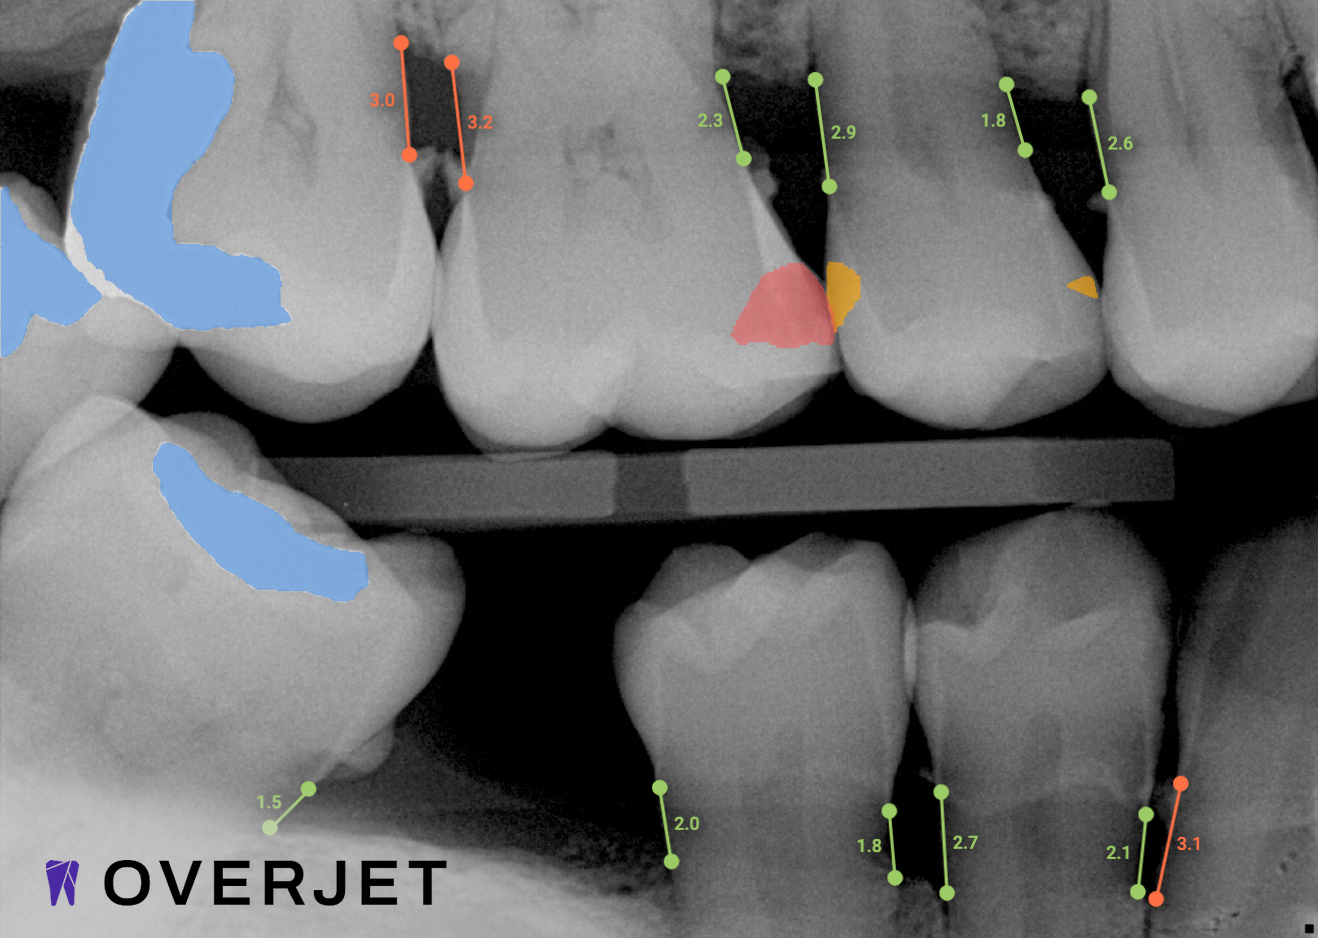

Confidence in Your Diagnosis

Our practice is proud to provide the best technology in the dental industry, including Overjet AI for instant X-ray analysis.

Overjet’s artificial intelligence technology transforms traditional black-and-white X-rays by adding a layer of data that instantly outlines decay (cavities) and measures bone loss. This makes it easy for you to see your results alongside your dentist.  It’s like getting a second opinion delivered instantly. With Overjet’s analysis and easy-to-read presentation, you will have the information you need to make an informed decision about your oral health. Together, we’ll review your findings and discuss the best steps to take to achieve your goals.